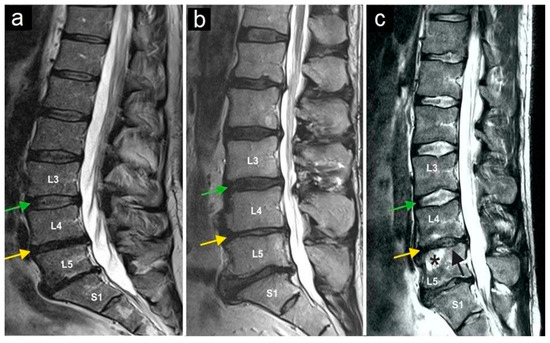

Figure 3.

Magnetic resonance imaging of three lumbar spine patients (a–c). The green arrows mark the L3/L4 disc, and the yellow arrows mark the L4/L5 disc. Note the normal structure of the L3/L4 disc, while the yellow arrows indicate a reduced intervertebral disc height (and thus the disc space) at L4/L5, as observed in all three patients. The star (c) marks bone marrow edema in vertebral body L5, and the black arrow (c) indicates the collapse of the superior endplate of the L5 vertebral body.